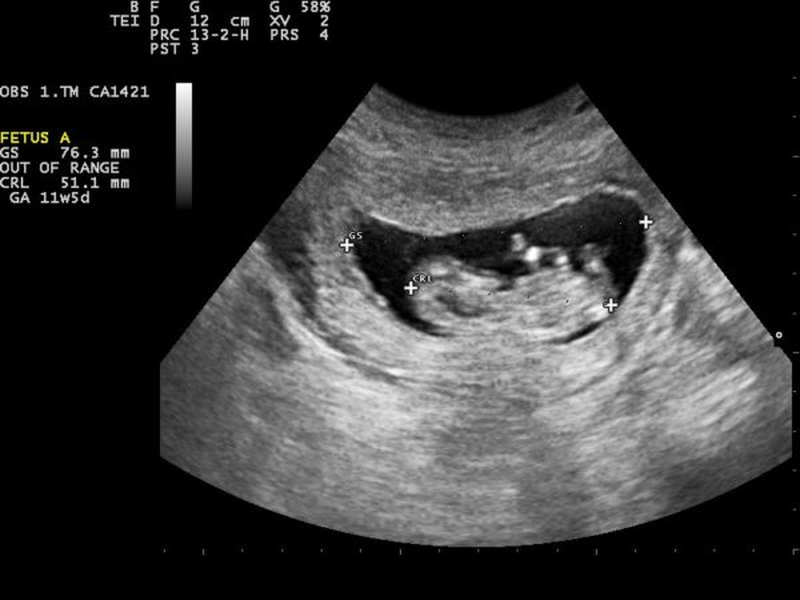

Theo nhiều bác sĩ chuyên khoa sản thì thường trung bình sau 6 tuần trứng đã thụ tinh sẽ có phôi thai, lúc này kích thước túi thai ở khoảng 18mm và xuất hiện phôi thai bên trong. Lưu ý sẽ xuất hiện các trường hợp túi thai phát triển bình thường nhưng không tìm thấy phôi thai, được biết đến là hình thức hư thai.

[GÓC GIẢI ĐÁP] Túi thai bao nhiêu mm thì có phôi thai? 1"Túi thai bao nhiêu mm thì có phôi thai?" là câu hỏi được nhiều sự quan tâm.